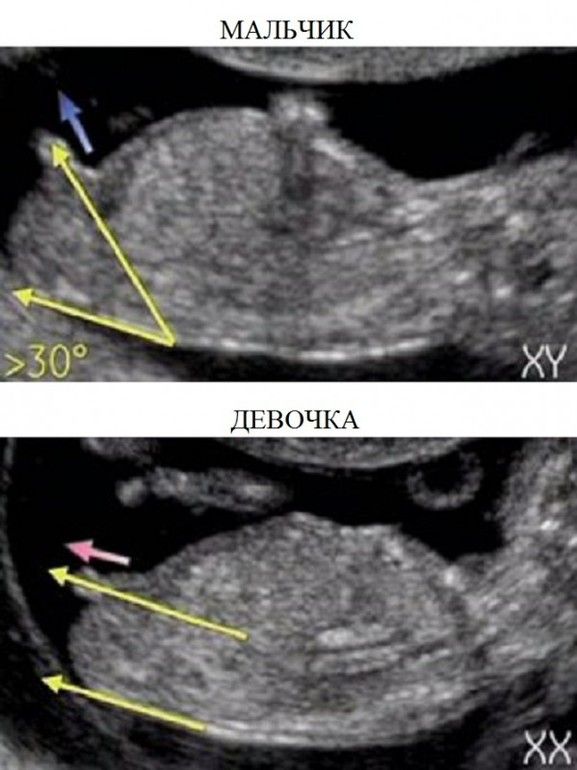

Изображение мальчик